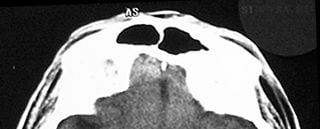

Find the thrombus.